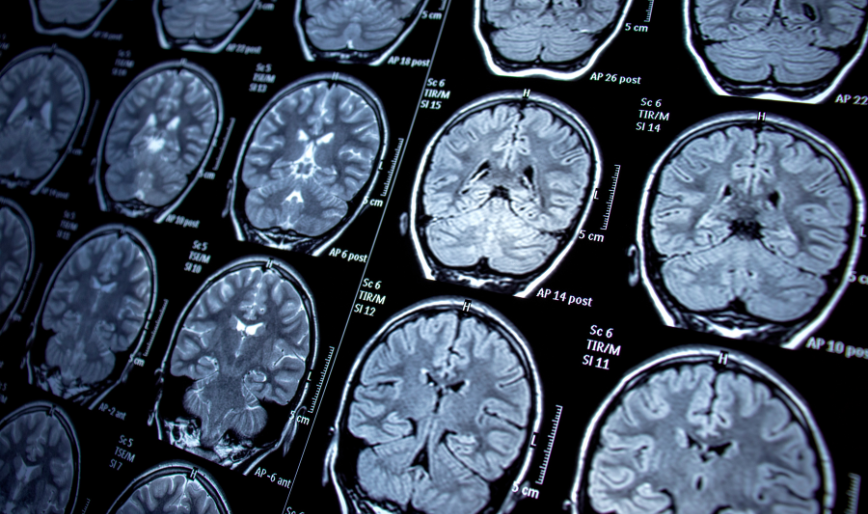

At R.K. Multispeciality Hospitals, our Neurosurgery department is dedicated to providing expert surgical care for complex brain and spine conditions. We specialize in treating a wide range of neurological disorders, utilizing advanced techniques to ensure the highest level of precision and patient safety.

Our neurosurgery team combines state-of-the-art technology with meticulous surgical expertise to address both urgent and chronic neurological conditions. We focus on minimizing risks and maximizing recovery, ensuring each patient receives personalized, comprehensive care.